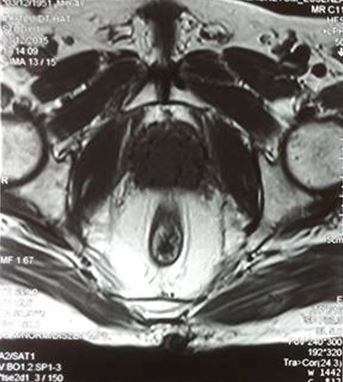

• Siêu âm, MRI tiểu khung tiền liệt tuyến to khoảng 25 g, khối u TLT chưa xâm lấn túi tinh

• PSA: 28,5ng/ml

Trên hình ảnh MRI, khối u tuyến tiền liệt ranh giới rõ, bắt thuốc mạnh, kích thước 15 mm, chưa xâm lấn vỏ bao và túi tinh 2 bên.

• Bệnh nhân được sinh thiết TLT qua đường trục tràng. Mô bệnh học: Ung thư biểu mô tuyến, điểm Gleason 6

• Xạ hình xương, CT ngực: chưa di căn

Bệnh nhân được chẩn đoán K tuyến tiền liệt, T2cNoMo, Gleason 6 điểm, có chỉ định cấy hạt phóng xạ

Tiến hành cấy hạt phóng xạ: 21 kim, 66 hạt, tổng liều I-125: 145 Gy